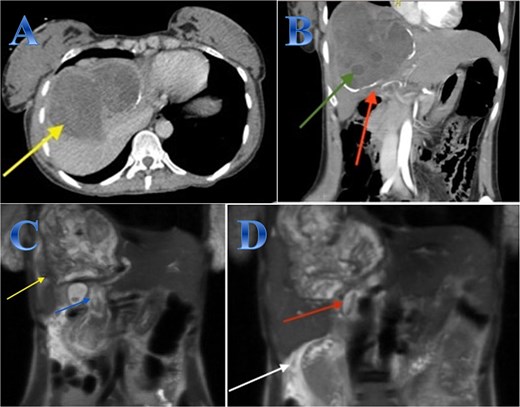

A 54-year-old woman presented with upper abdominal pain with a history of PAIR procedure before 5 years. The abdominal CT scan with contrast highlights left hepatic lobe calcified exophytic CE (Fig. 3).

Case 3. (A) Coronal CT cut of the abdomen at venous phase showing a well-defined cystic lesion (hydatid cyst) seen at the left hepatic lobe, showing calcifications, the lesion seen partially exophytic from the liver and abutting the lesser curvature of the stomach. (B & C) The hydatid cysts that were resected from the liver (C) and from the greater Omentum (B). (D) After resection the liver hydatid cyst was opened to examine the content of the cyst which is showing jelly like structure.

For a left lateral hepatic resection, a subcostal incision allowed exploration of the calcified cystic mass, which affected segments 2 and 3 of the liver and was significantly adhered to the diaphragm and stomach. A left lateral segment (segments 2 and 3) mobilization procedure required dividing the falciform, left triangular, and left coronary ligaments. A harmonic scalpel, in combination with bipolar coagulation, completed the resection of the recurrent hydatid cyst without damaging its internal contents (Fig. 3).